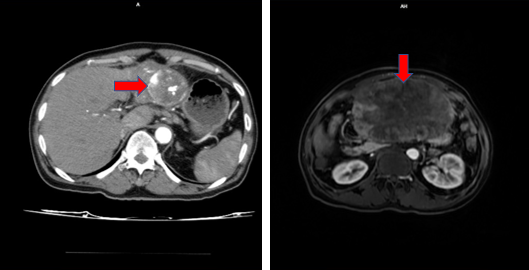

Tháng 1/2024 bệnh nhân đau bụng nhiều, vào viện được chụp CT ổ bụng có hình ảnh nhu mô gan phải có khối lớn kích thước 130x94x108 mm, ranh giới khá rõ, trong có các đám tăng tỉ trọng dạng vật liệu can thiệp và giảm tỷ trọng dạng hoại tử, ngấm thuốc mạnh không đồng nhất thì động mạch, thải thuốc thì tĩnh mạch.

Hình 4. Hình ảnh khối ngấm thuốc nhu mô gan phải, tăng kích thước nhiều so với phim chụp tháng 11/2023